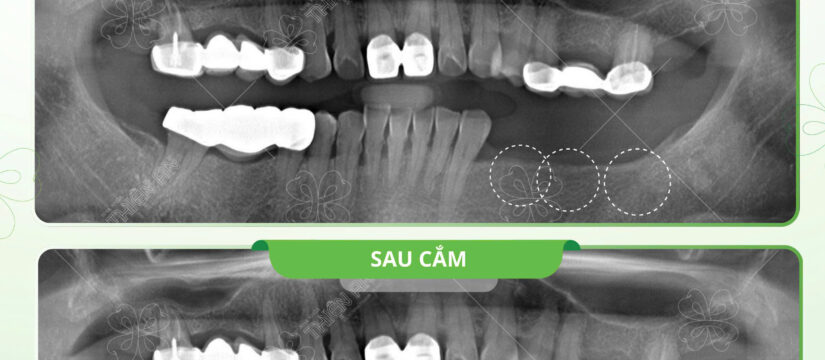

Hoàn thành cắm 3 trụ implant nhanh chóng phục hồi khả năng ăn nhai cho cô T tại Nha khoa Thiện An????

Completed 3 implants to quickly restore Ms. T’s ability to eat and chew at Thien An Dental Clinic????

✨Răng hàm là răng ăn nhai chính, nhưng khi bị mất răng quá trình ăn nhai bị ảnh hưởng. Lâu ngày bị tiêu xương và các răng xung quanh bị ảnh hưởng không hề nhẹ.

Molars are the main chewing teeth, but when teeth are lost, the chewing process is affected. Over time, bone loss and surrounding teeth are not lightly affected.